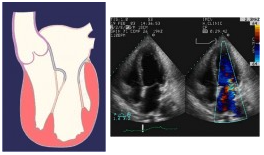

Infine, una insufficienza mitralica di tipo III (con limitato movimento dei lembi), è dovuta a irrigidimento e retrazione dei lembi o a calcificazioni, secondari a patologia reumatica o endocardite infettiva, oppure può essere dovuta a dilatazione dell’anulus con cedimento e/o retrazione dei lembi, come si può verificare in corso di cardiopatia ischemica cronica o di cardiomiopatia dilatativa, o a infarto, più frequentemente posteriore, che provoca retrazione del lembo posteriore.

Insufficienza mitralica di tipo IIIb, dovuta a limitazione dei lembi valvolari durante la sistole.